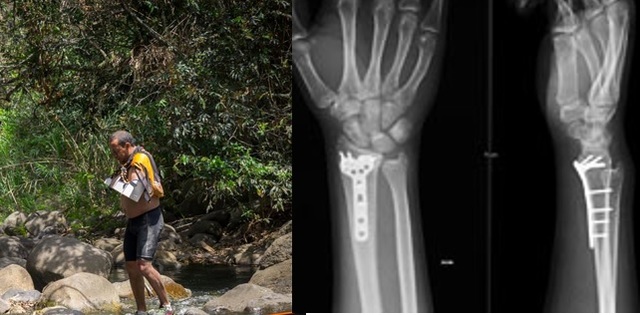

• Me fracturo la muñeca izquierda

Me fracturo la muñeca izquierda

En pacho Cundinamarca sufro un accidente haciendo ciclomontañismo, lo cual dejó como resultado la fractura del radio distal de la mano izquierda.